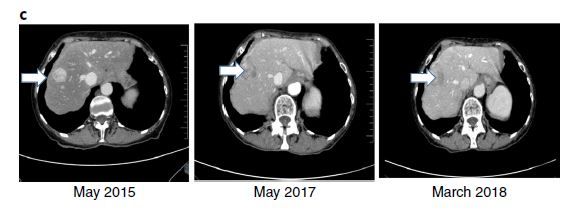

第二个病人,是一个标准治疗失败的晚期肠癌患者,这个病人当时已经上市的靶向药、化疗药都尝试过了。基因检测发现MSH6突变,导致了DNA错配修复缺陷,因此主管专家推荐试一试PD-1抗体(病人是2015年年初用药的,当时PD-1抗体尚未批准用于MSI的肠癌,这项批文是2017年5月才批准),用药后疾病明显缓解,疗效维持时间已经超过3年。